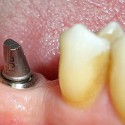

Foto 4: Corona in porcellana finale

Foto 6: Il sorriso finaleIl paziente portava da diversi anni una corona in porcellana sorretta da un perno posto all’interno del canale della radice del 22 (incisivo laterale superiore sinistro).

Un processo carioso a carico della radice non permetteva la stabilità della corona e del suo perno (la corona in porcellana si staccava continuamente).

In questo caso la terapia d’elezione era l’estrazione della radice e l’inserimento di un impianto endosseo. Si è potuto procedere con la tecnica immediata e flapless cioè, estratta la radice viene inserito l’impianto senza tagliare la gengiva per sollevare il lembo di tessuto gengivale.

Tale tecnica, spesse volte, non è aplicabile perché, in mancanza di osso intorno alla radice, occorre rigenerarlo per inserire successivamente l’impianto.